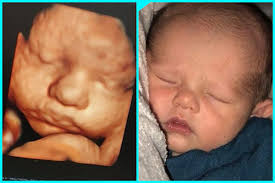

These before and after images are from actual 3d/4d ultrasound sessions performed at pregnantsee!you will enjoy the same view of your little one and even see full motion video of your unborn baby. 18 week hd live/4d ultrasound. Ultra sound beim führenden marktplatz für gebrauchtmaschinen kaufen. Full service 3d/ 4d ultrasound photography studio. Feb 9, 2015 at 8:07 pm. The only difference is that with the 5d, you can obtain sharper and better resolution images. It is fully formed and mostly filled out. It is a fun time for the ultrasound as many times you will see movements like smiling, eyes blinking, hands moving, and many other movements.

The baby has had time to build up body fat, but still has room to move around. Plus, learn about the major reproductive developments at this stage. 3d/4d ultrasounds sessions should be remembered as good memories for years to come. A 3d/4d ultrasound taken of a baby that visited prenatal impressions, the only premier provider of 3d/4d ultrasounds in orlando, florida since 2005. It was a very special day for my husband and i.